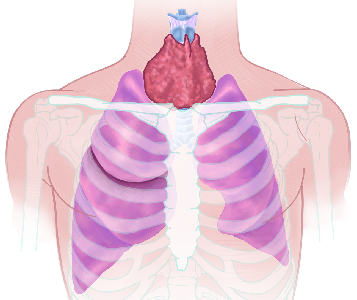

Detailreiche Fotografien aus der medizinischen Praxis ergänzen die Texte; moderne, genaue,

wissenschaftliche Zeichnungen geben Einblick in die Anatomie und die Funktion der Lunge und

anderer Organe.